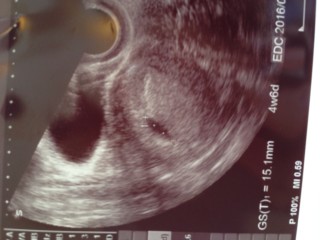

ちょうど1センチの胎嚢さん! 卵黄嚢も無事みえて、赤さんは来週くらいには見えるかなぁ~